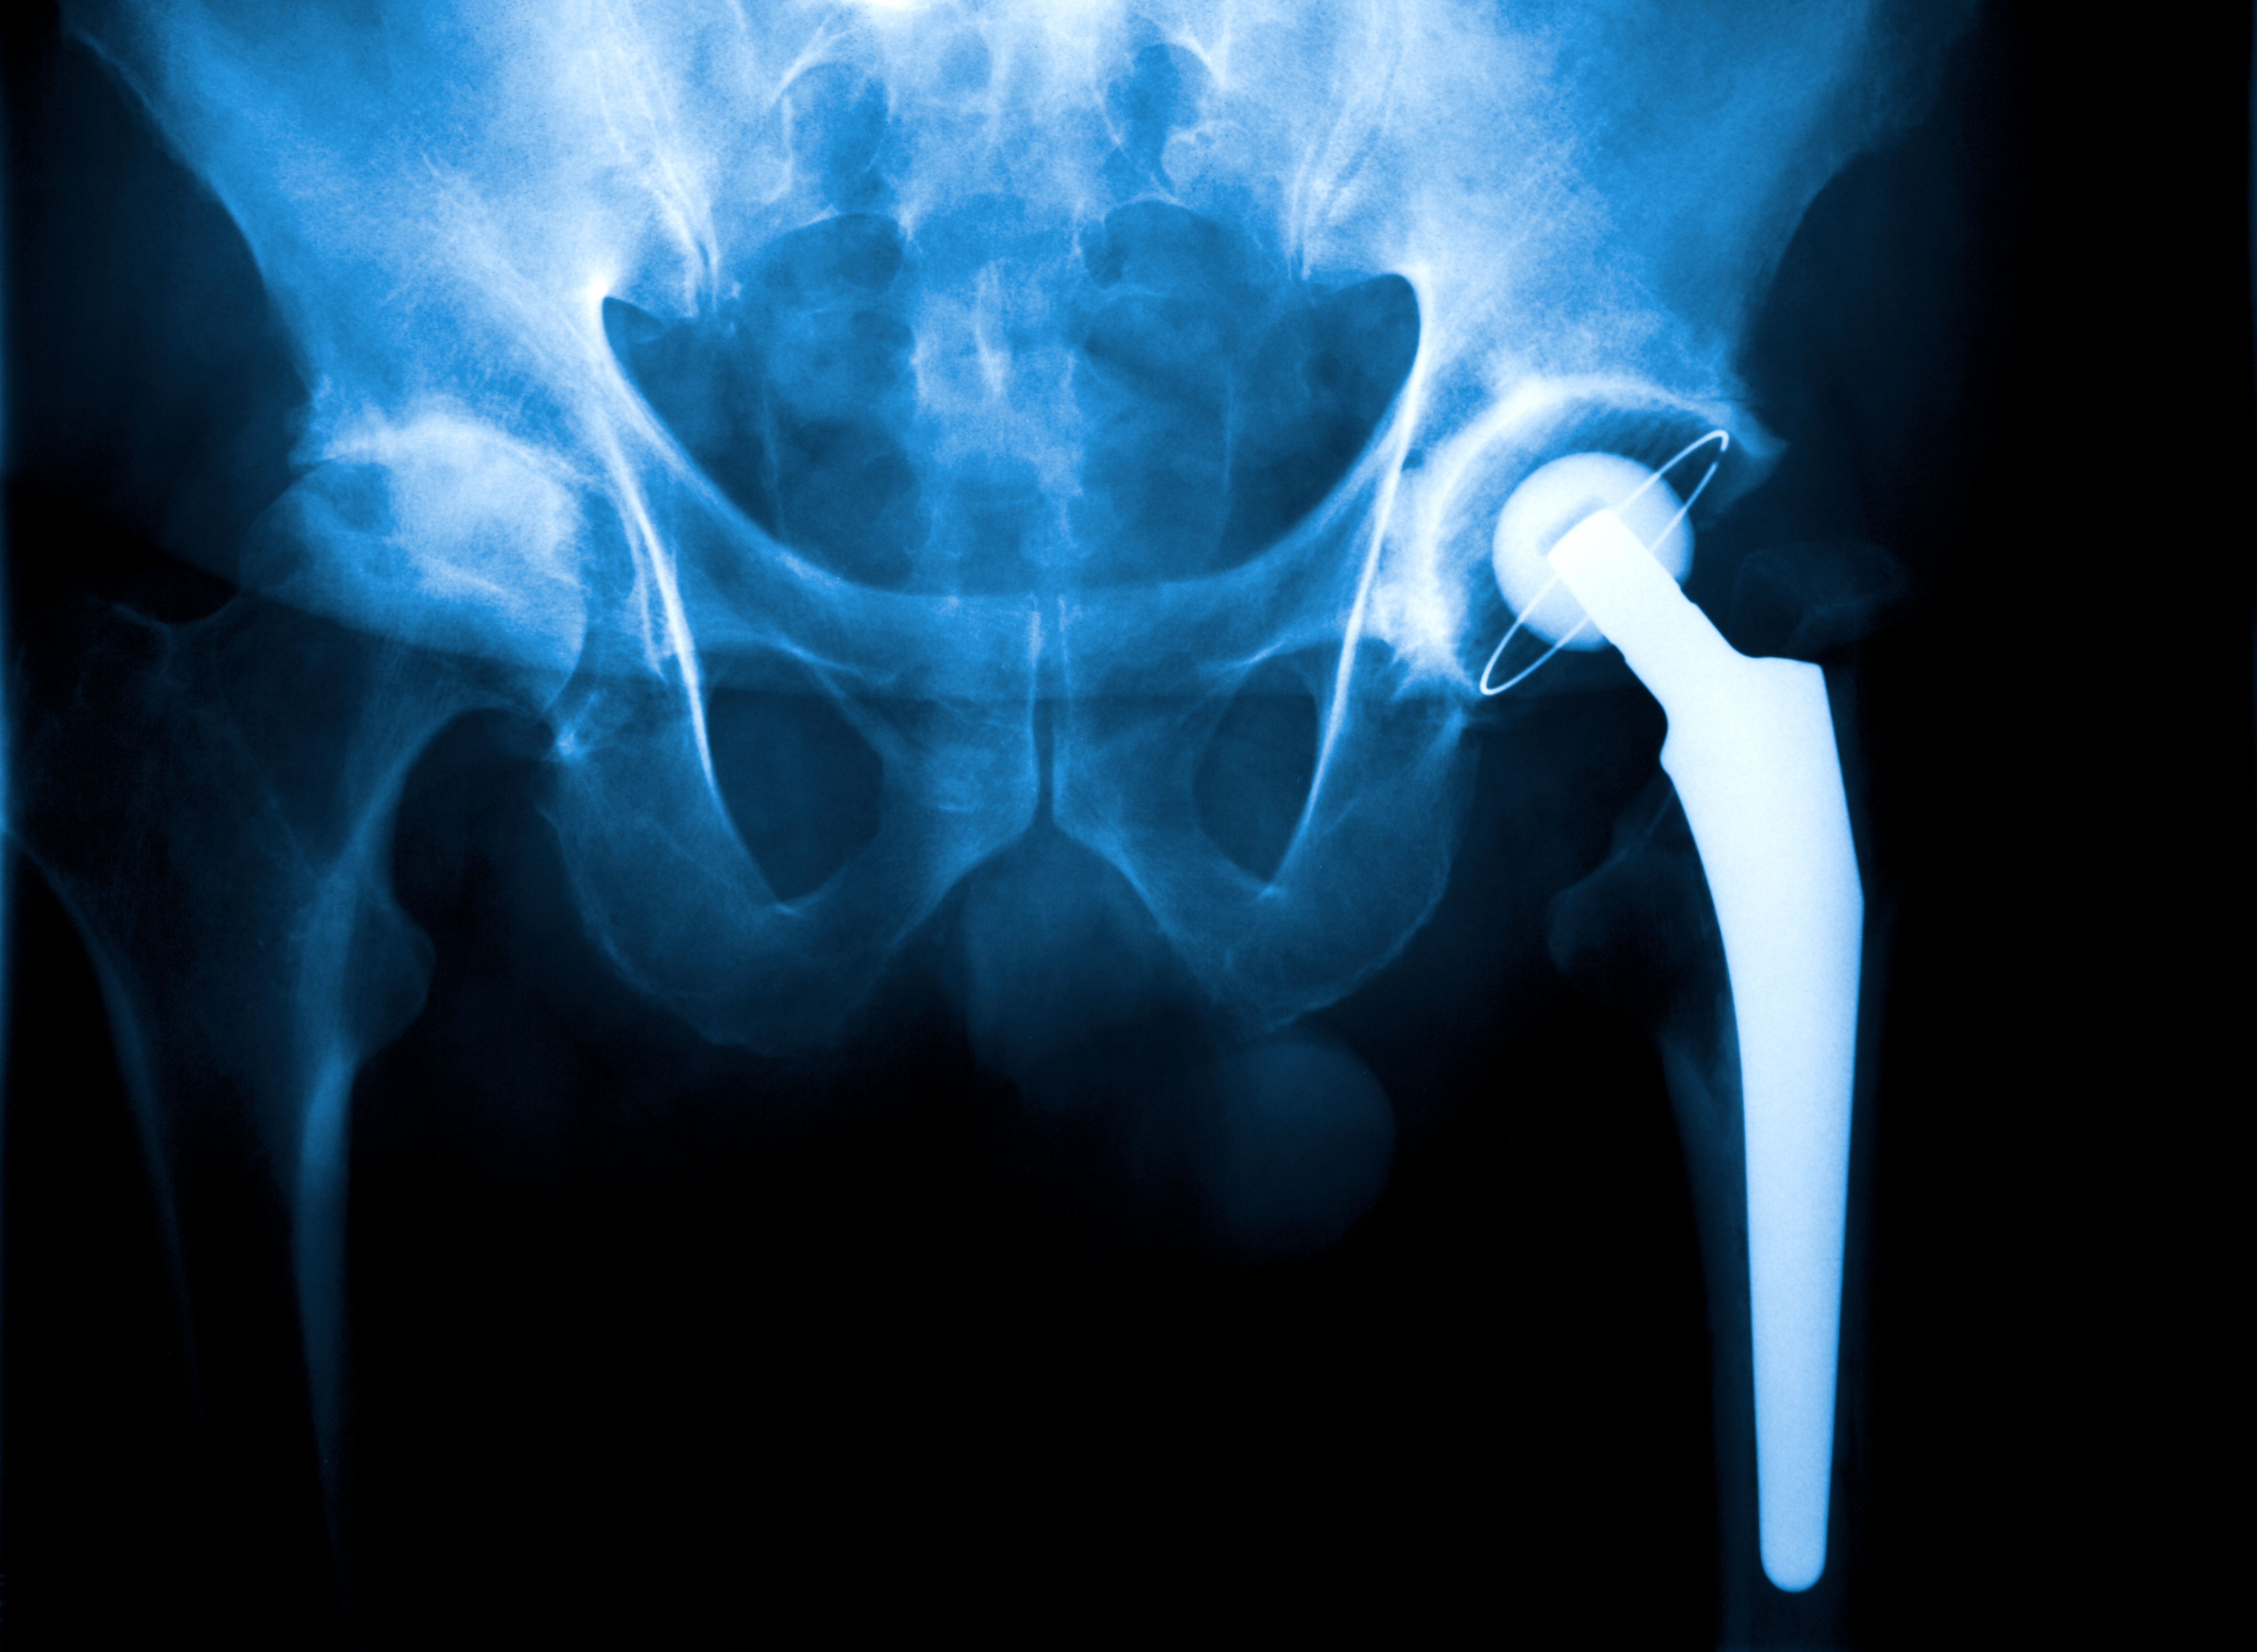

Årlig opereres rundt 3 500 pasienter med hemiprotese for lårhalsbrudd ved norske sykehus. Pasientgruppen har en gjennomsnittsalder på over 80 år og høy forekomst av benskjørhet og andre tilleggssykdommer (1). Flesteparten oppnår ikke det funksjonsnivået eller den livskvaliteten som de hadde før bruddet inntraff, og én av fire pasienter dør innen ett år (2). Mens lårhalsbrudd ute av stilling tidligere ble operert med skruefiksasjon, opereres nå nesten alle med protese, fordi flere studier har vist bedre livskvalitet, bedre hoftefunksjon og færre reoperasjoner ved bruk av protese sammenlignet med skruefiksasjon. De vanligste reoperasjonsårsakene etter protesekirurgi er infeksjon, at protesen går ut av ledd og protesenære brudd (1).

Et protesenært brudd er en sjelden, men alvorlig komplikasjon. I noen tilfeller hvor protesen sitter fast og bruddet er stabilt, kan et slikt brudd behandles uten ny kirurgi, men vil ofte innebære smerter, immobilisering og dårligere hoftefunksjon. I de fleste tilfeller er imidlertid et nytt og omfattende kirurgisk inngrep nødvendig, enten osteosyntese med en lang metallplate på lårbenskaftet eller utskifting av hele protesen (3). Slik kirurgi kan føre til stort blodtap, tromboserisiko, smerter, nedsatt hoftefunksjon samt langvarig rehabilitering. En reoperasjon er forbundet med redusert funksjonsnivå, høy morbiditet og høy mortalitet (4–6).

I tråd med internasjonale studier viser studier med data fra Nasjonalt hoftebruddregister (8) økt risiko for reoperasjon grunnet protesenære brudd ved bruk av usementerte protesestammer sammenlignet med sementerte stammer. I de nasjonale retningslinjene anbefales derfor bruk av sementerte lårbensproteser til alle pasienter med akutt lårhalsbrudd som er ute av stilling (9). Likevel er det flere sykehus som fortsatt bruker usementerte protesestammer.

Videre er det forskjellige design på de sementerte protesestammene som blir benyttet i Norge. Protesenære brudd oppstår nesten utelukkende ved bruk av protesestammer som er glatte og kileformede, og sjelden ved bruk av rette og anatomiske protesestammer med matt overflate (10, 11). Glatte kileformede stammer har vært de mest brukte protesene i Norge de siste årene (1), og de har svært gode resultater i studier av yngre artrosepasienter med god benkvalitet. Hos eldre hoftebruddpasienter med dårlig benkvalitet gir de dessverre øket risiko for protesenære brudd.

Hvilken protesetype som skal benyttes, har tradisjonelt vært bestemt på sykehusnivå etter en anbudsprosess. Anbudet danner grunnlaget for hvilken behandling som tilbys og hvilke resultater som kan oppnås. Det har vært vanlig at sykehus har valgt én protesetype uavhengig av om operasjonen er for artrose eller hoftebrudd. I tråd med internasjonale og norske studier bør man differensiere behandlingen og velge en protese med rett eller anatomisk sementert stamme til hoftebruddpasienter med dårlig benkvalitet. Hoftebruddpasienter utgjør en eldre og skrøpelig pasientgruppe som fortjener den best dokumenterte behandlingen uavhengig av hvilket sykehus pasienten tilhører.